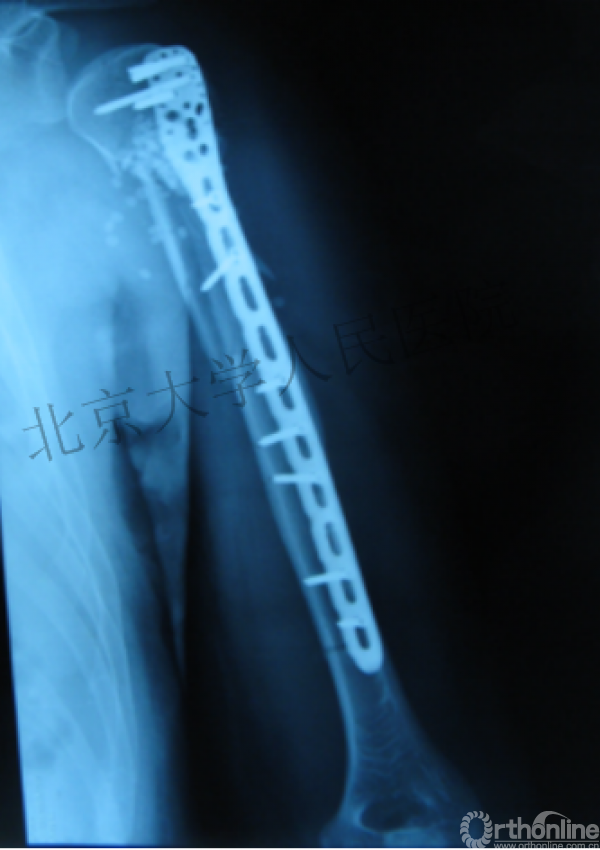

内侧皮质粉碎,低位外科颈骨折,肱骨头-干角维持困难。

术后复位丢失,肱骨头内翻畸形。

能否该偏心固定(钢板)为髓内固定,增加力臂?

早知今日,何必当初?

此时对比髓内钉是不是有很大优势?